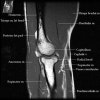

팔꿈치 관절의 MRI 단면 영상

1. Coronal section

1) Collateral ligament

2) Common extensor/flexor tendon group patholgy as well as epicondylitis